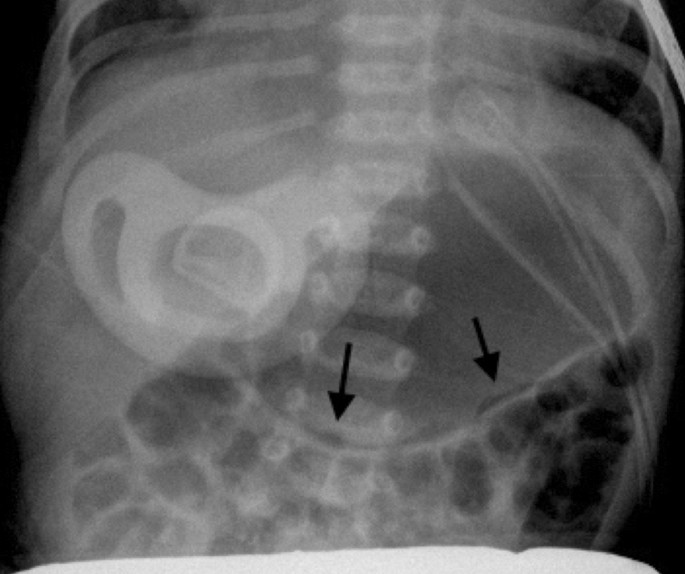

Nonspecific Bowel Gas Pattern. The interpretation nonspecific abdominal gas pattern should be avoided. Mild localized ileus or sentinel loop. Page Contents1 OVERVIEW2 ORIENTATIONS USED FOR ABDOMINAL X-RAYS3 ANATOMY ON ABDOMINAL X-RAY4 APPROACH GECkoS5 GAS PATTERN INTRALUMINAL6 EXTRALUMINAL GAS7 CALCIFICATIONS8 SOFT TISSUE MASSES OVERVIEW This page is dedicated to providing a guide on the approach to interpreting an abdominal X-ray. Posted 532012 330 PM GMT -7 Has anybody has this.

In patients with acute abdominal symptoms who have normal or abnormal but nonspecific bowel gas pattern on abdominal plain films CT is recom- mended see Fig. ICD-10-CM Diagnosis Code K59. Nonspecific bowel gas pattern. It is Non-Specific Bowel Gas Pattern. A physiological stool burden means you have a normal amount of stool in your colon. The radiology report is the primary means of communication between the radiologist and the referring physician.

Functional disorders of stomach K31- ICD-10-CM Diagnosis Code K59. Hover onoff image to showhide findings. This phrase is often used when the bowel gas pattern is not specific for a small bowel obstruction. We found the definition to be dichotomous and asynchronous between radiologists and their referring physicians. Furthermore there is a wide range of meaning of the term among radiolo- gists because the criteria used are individual and sub- jective. 6 A recent survey of community-based teaching hospital radiolo- gists showed that 70 of the radiologists used this term.

Bowel gas patterns may point to an underlying cause bowel gas patterns include. This phrase is often used when the bowel gas pattern is not specific for a small bowel obstruction. Small bowel air usually appears as multiple small randomly distributed gaseous foci scattered throughout the abdomen. I suggest you look the article by. Emergency R a d i o l o g y M a y J u n e 1996 further.

The bowel gas pattern is normal. It is Non-Specific Bowel Gas Pattern. Infectious Disease 33 years experience. This doesnt help the ordering physician much except to tell him to use his clinical suspicion to guide further workup. Page Contents1 OVERVIEW2 ORIENTATIONS USED FOR ABDOMINAL X-RAYS3 ANATOMY ON ABDOMINAL X-RAY4 APPROACH GECkoS5 GAS PATTERN INTRALUMINAL6 EXTRALUMINAL GAS7 CALCIFICATIONS8 SOFT TISSUE MASSES OVERVIEW This page is dedicated to providing a guide on the approach to interpreting an abdominal X-ray.

Dilatation 3cm of the small bowel is considered abnormal however the longer the segment of bowel that is dilated the more likely bowel dilatation represents a genuine obstruction. Functional disorders of stomach K31- ICD-10-CM Diagnosis Code K59. Change in bowel habit NOS R194. Im only addressing the first question. Nonspecific bowel gas pattern.

X-ray The bowel gas pattern appears unremarkable. It basically means that the appearance of bowel is unclear on the X-ray and can be normal or abnormal. Page Contents1 OVERVIEW2 ORIENTATIONS USED FOR ABDOMINAL X-RAYS3 ANATOMY ON ABDOMINAL X-RAY4 APPROACH GECkoS5 GAS PATTERN INTRALUMINAL6 EXTRALUMINAL GAS7 CALCIFICATIONS8 SOFT TISSUE MASSES OVERVIEW This page is dedicated to providing a guide on the approach to interpreting an abdominal X-ray. ICD-10-CM Diagnosis Code K59. See the page on normal Bowel Gas Pattern.

See the page on normal Bowel Gas Pattern. Non-Specific Bowel Gas Pattern - How is Non-Specific Bowel Gas Pattern abbreviated. CONCLUSIONS Radiologists use the term nonspecific gas pattern to denote a gas pattern that is not quite normal but that does not fulfill the criteria of a more specific diagnosis such as small bowel obstruction. The radiology report is the primary means of communication between the radiologist and the referring physician. The term nonspecific abdominal gas pattern should be abandoned because it may signify a normal condition or a pathologic state.

The interpretation nonspecific abdominal gas pattern should be avoided. We found the definition to be dichotomous and asynchronous between radiologists and their referring physicians. Furthermore there is a wide range of meaning of the term among radiolo- gists because the criteria used are individual and sub- jective. This type of scan is also sometimes. We all have gas in our bowels and a non obstructive bowel gas pattern means it looks like it should look.

Slide 2 of 3. A normal small bowel gas pattern varies from no gas being visible to gas in three or four variably shaped small intestinal loops. NSBGP is a shorter form of Non-Specific Bowel Gas Pattern. Nonspecific bowel gas pattern. We all have gas in our bowels and a non obstructive bowel gas pattern means it looks like it should look.